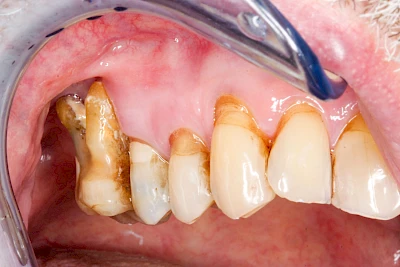

Ist zunächst nur das Zahnfleisch von der Entzündung betroffen, spricht man von Gingivitis. Später, wenn auch der Knochen um die Zähne herum entzündet ist, spricht man von einer Parodontitis. Bei der Parodontitis wird der Knochen nach und nach abgebaut und das Zahnfleisch zieht sich zurück. Die Zahnhälse und Zahnwurzeloberflächen liegen mehr und mehr frei. Die Zähne werden zunehmend lockerer und fallen schließlich aus.